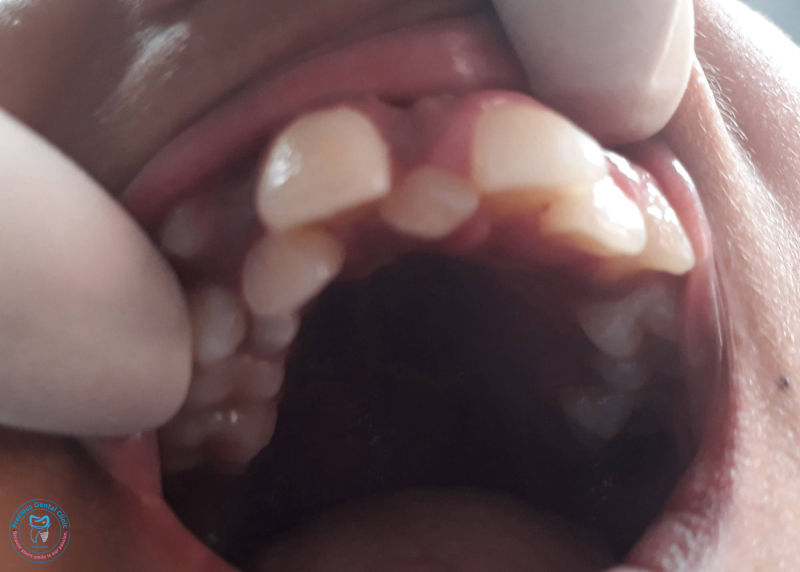

Collection of photos, here you will find the photos of doctor, services, environment and work.